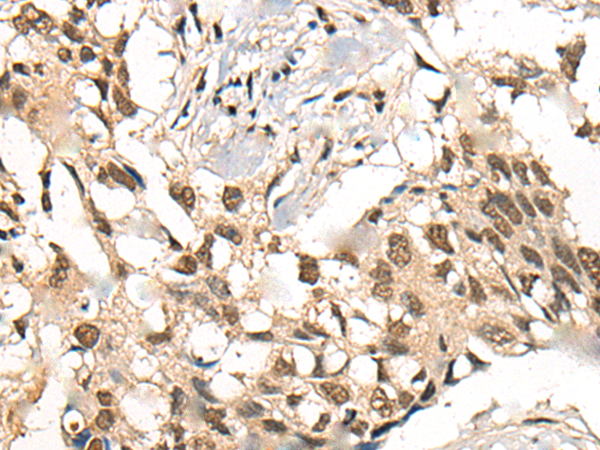

IHC positive control: |

Human esophagus cancer and Human lung cancer |

IHC Recommend dilution: |

20-100 |